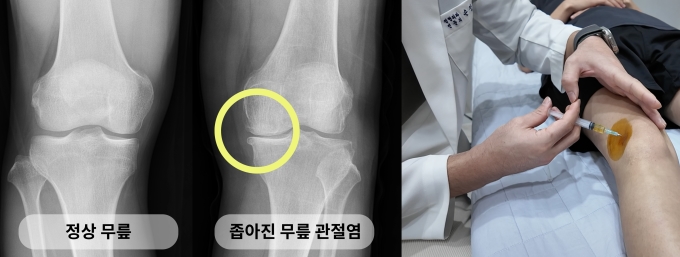

걷기만 해도 무릎이 붓거나 통증이 반복되고 계단을 오르내릴 때 불편감이 심해지는 경우에는 관절염 가능성을 점검해볼 필요가 있다. 청주 윈윈정형외과 의료진은 무릎 통증 관리의 핵심 요소로 허벅지 근력(대퇴사두근)을 꼽았다. 허벅지 근력이 부족하면 관절에 가해지는 부담이 커져 통증 악화와 기능 저하로 이어질 수 있다.

윈윈정형외과 손정인 원장은 "관절염은 진행 단계에 따라 치료 목표와 접근 방식이 달라진다"며 "초기부터 3단계까지는 상태에 따라 다양한 비수술적 치료와 주사치료를 고려할 수 있고 PRP(자가 혈소판 풍부 혈장) 주사치료 역시 수술을 고민하는 환자에게 하나의 선택지가 될 수 있다"고 말했다.

이어 "보행 시 통증이 심하고 기능 저하가 뚜렷한 4단계의 경우에는 수술적 치료를 통해 보행 기능 회복을 도모하는 것이 장기적인 관점에서 도움이 될 수 있다"고 덧붙였다.